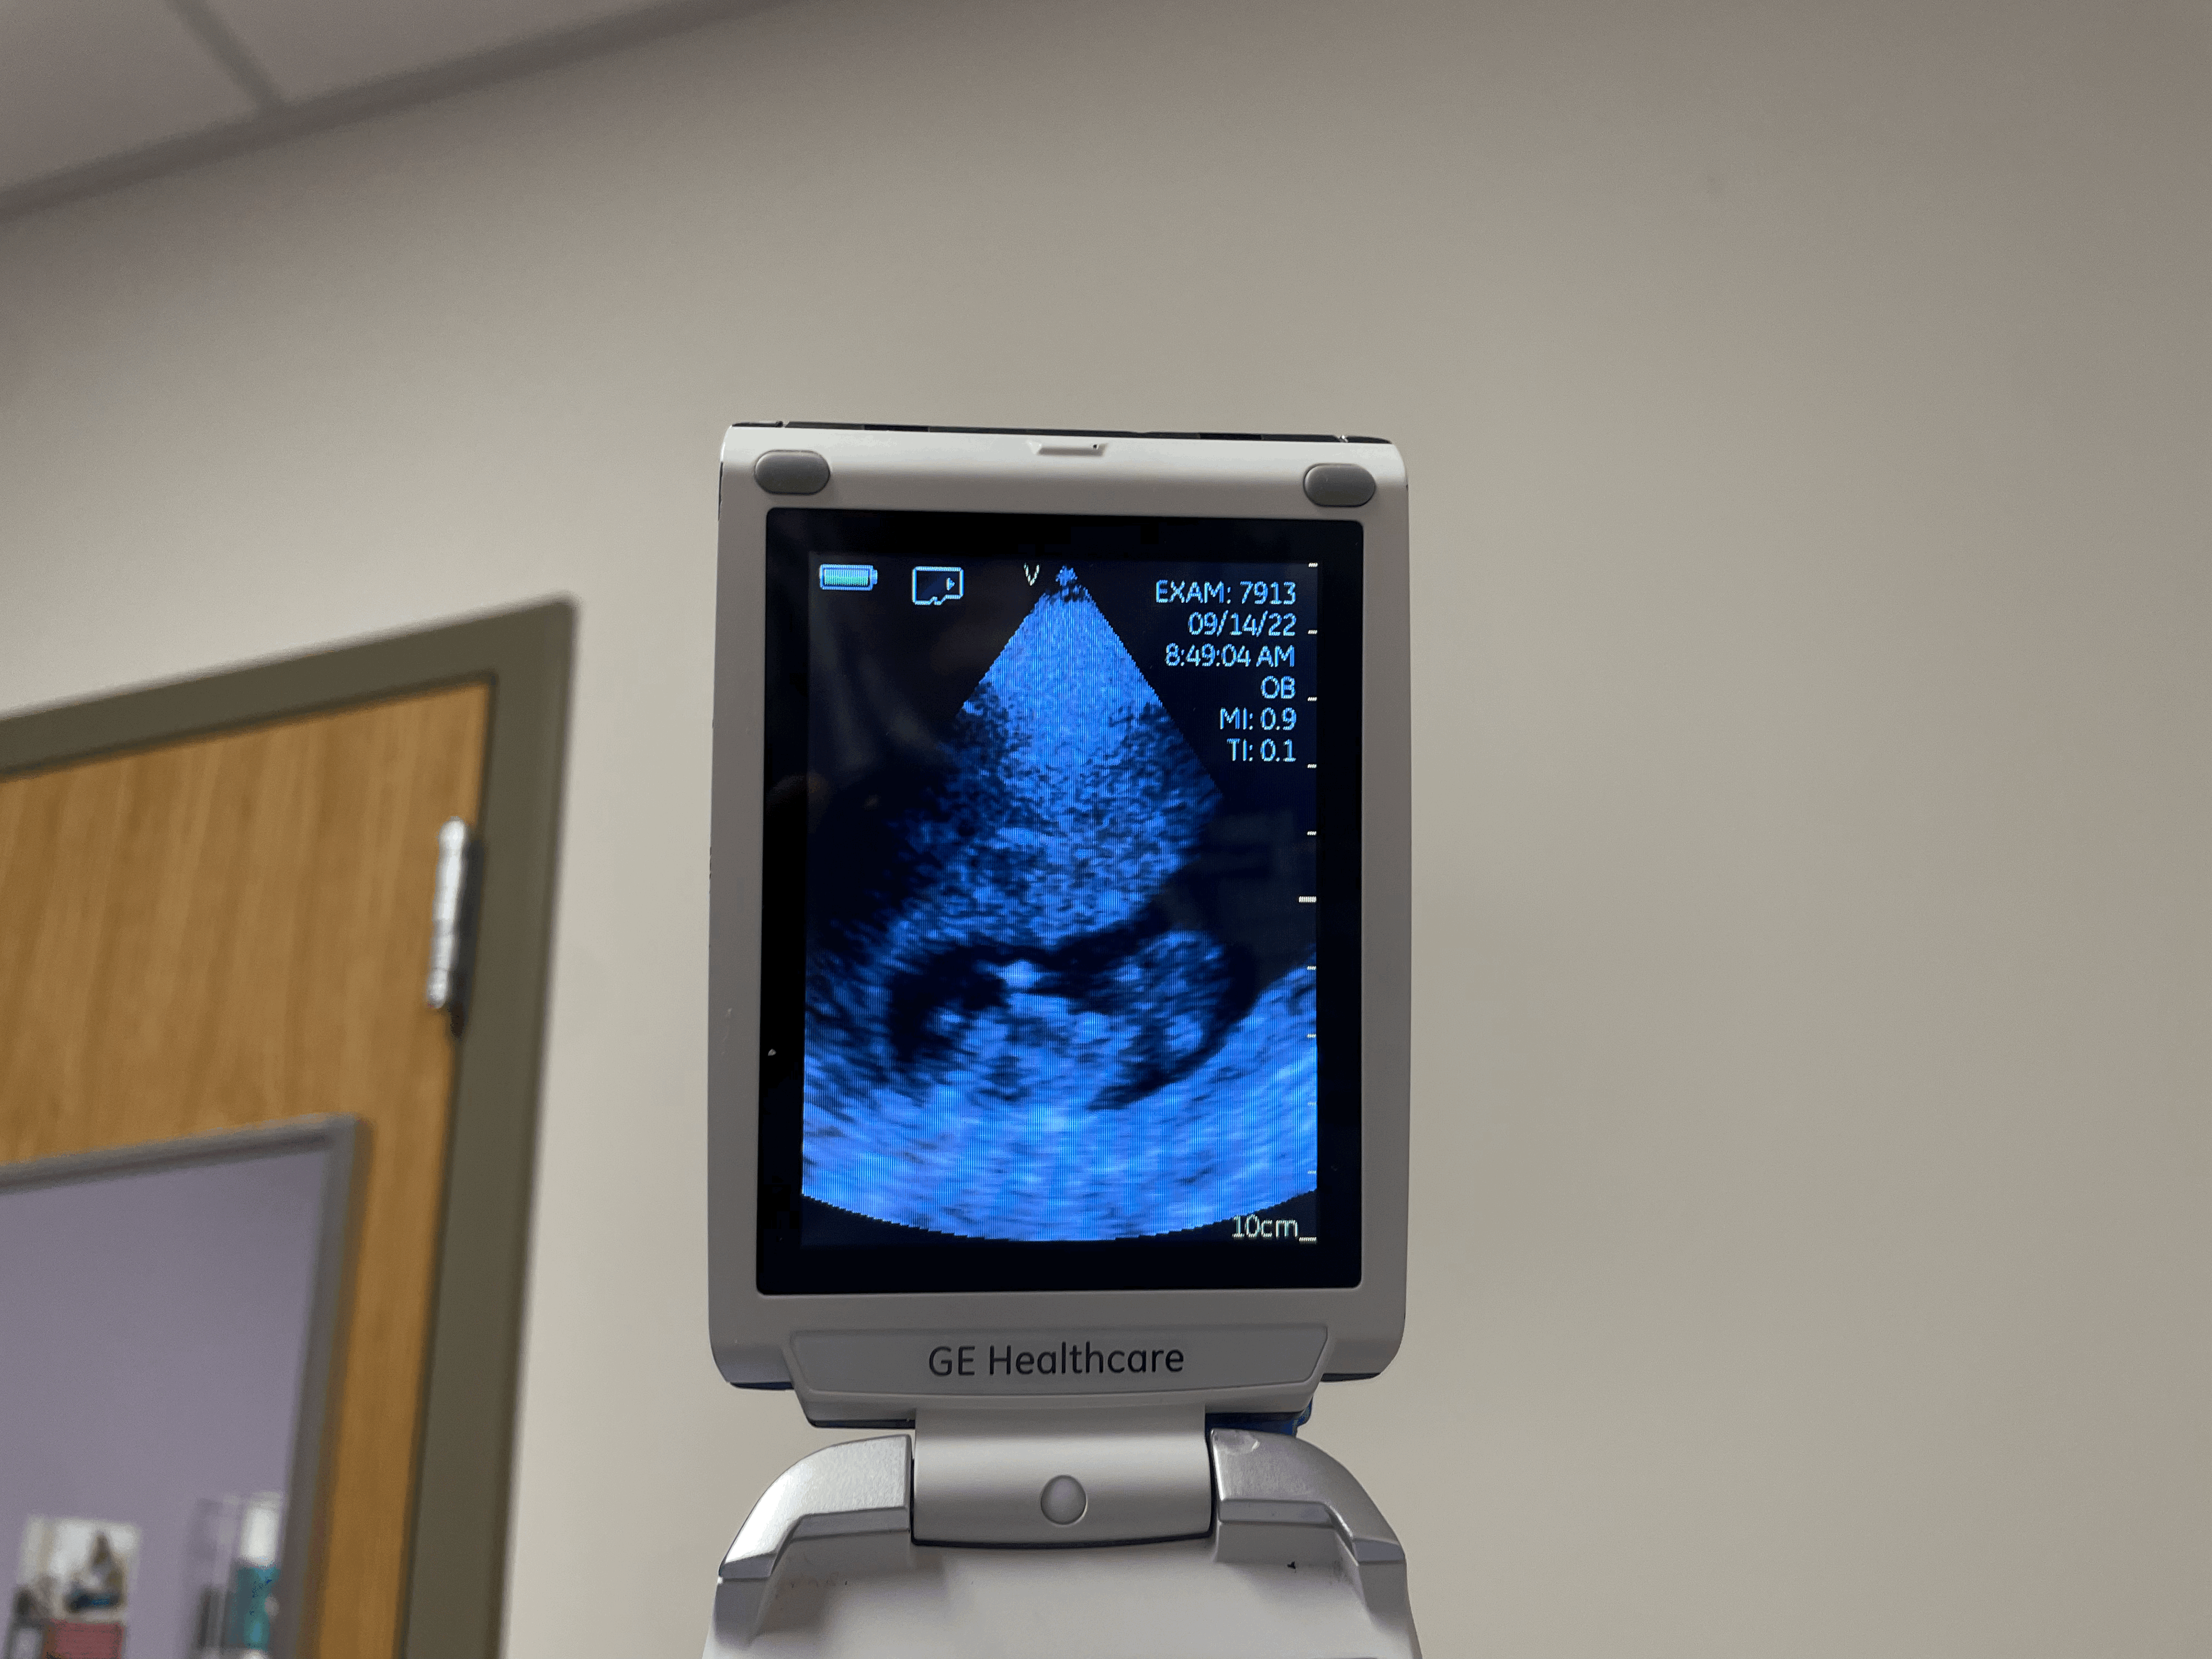

Pap test가 끝나고 옛날 폴더 폰 처럼 생긴 휴대용 초음파 기계를 가져와서 간단하게 초음파를 봐줬다.

Heartbeat 들려주고 아이가 잘 자라고 있는지 확인 해 줬다.

사진을 뽑아주지 않아서 아쉬웠지만, 핸드폰으로 사진이나 영상은 찍을 수 있게 해줘서 그나마 다행이였다😅

이렇게라도 뽈뽈이가 잘 자라고 있다는 것을 보니 안심이 되고 뿌듯했다.

심장박동도 들려주는데, 우리는 첫 appointment에서 심장소리는 못 들어서 오늘 처음으로 뽈뽈이 심장소리를 들었다!

감동감동🥹 뽈뽈이가 움직이는 것도 봤는데 너무 귀여웠다!!

휴대용 초음파로 본 우리 뽈뽈이🥰 무럭무럭 잘 자라는 중💕